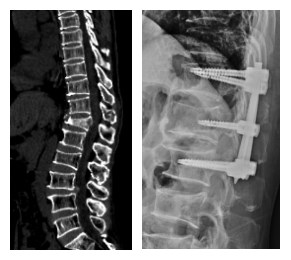

經(jīng)皮椎弓根螺釘內(nèi)固定術(shù)主要適用于中青年及身體條件較好、可耐受釘棒內(nèi)固定手術(shù)的胸腰椎骨折患者,手術(shù)時(shí)間1-2小時(shí),出血20ml,手術(shù)切口為6個(gè)長(zhǎng)度約1.5cm切口,術(shù)后1天可下地活動(dòng),術(shù)后4-7天可出院。

例:40歲男性,診斷為“胸12椎體壓縮性骨折”,在機(jī)器人輔助下行后路骨折閉合復(fù)位、經(jīng)皮椎弓根螺釘內(nèi)固定術(shù),術(shù)后椎體高度基本恢復(fù)正常。